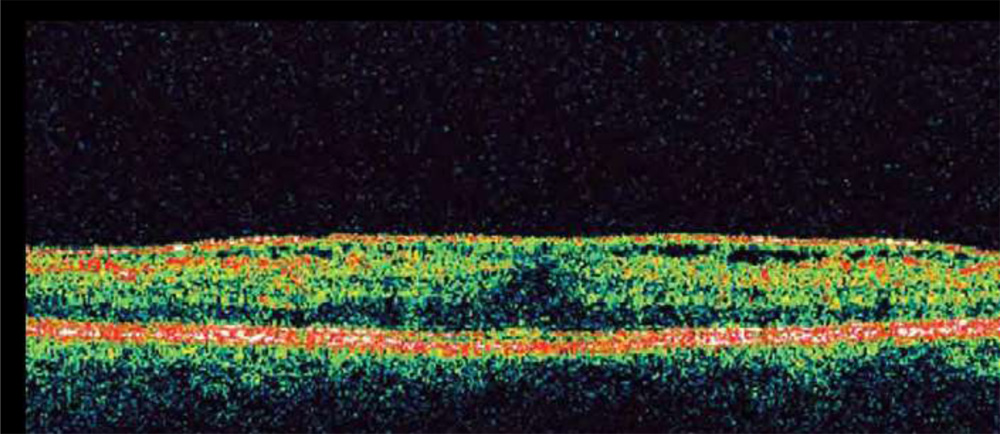

(a) ERM following cryotherapy of a peripheral retinal break. (b) OCT showing highly reflective ERM, corrugation of retinal surface, loss of foveal depression, and increased central macular thickness

OCT can play an important role in the clinical assessment of eyes with ERMs.

OCT can not only detect ERMs, but also assist in topographic localization, identification of vitreoretinal relationships (such as in the vitreomacular traction syndrome), detection of macular holes, and quantitation of macular thickness and macular volume.

Fig. OCT showing typical ERM features including highly reflective ERM, multiple points of retinal attachment, loss of foveal depression, and increased retinal thickness.